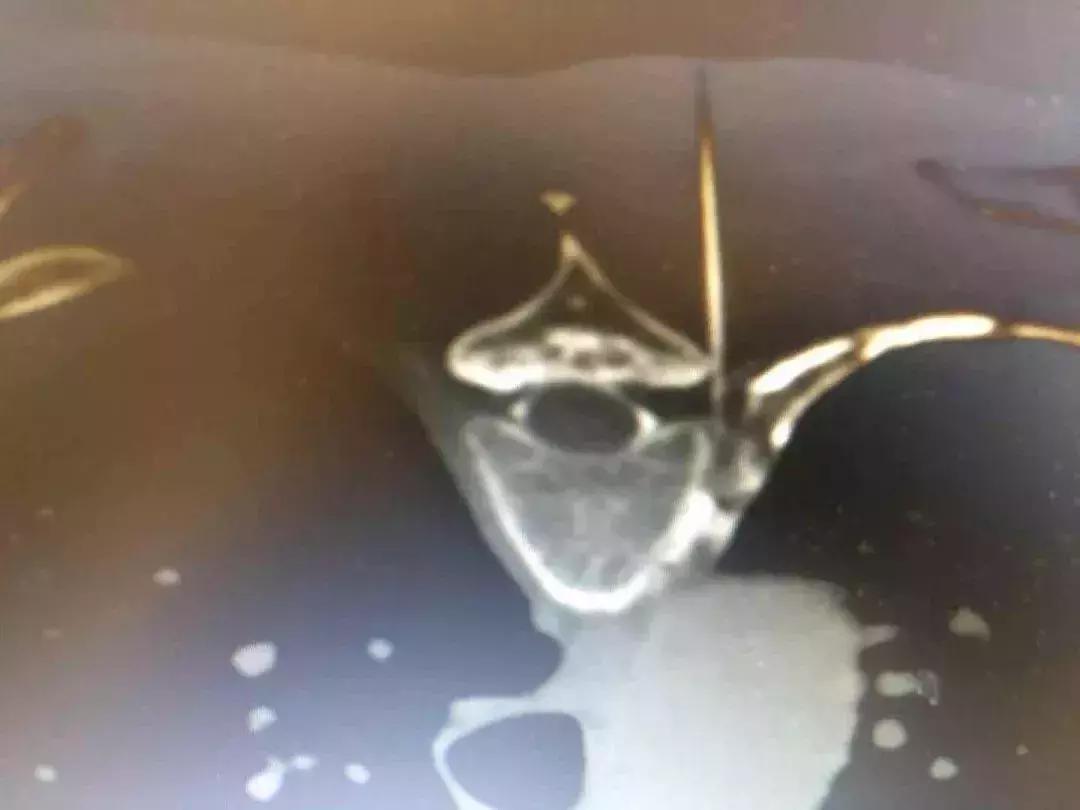

而针对吉老的症状,田医生给出了对应的治疗方案:CT引导下T3T4脊神经背根神节射频调控术+阿霉素注射术。其中的治疗原理就相当于对神经进行了一次“格式化”,把敏感的神经恢复到初始的空白状态,来降低对疼痛的传导性。它最大的优点就是在不破坏脊柱解剖结构和稳定性的基础上达到缓解症状的作用,具有创伤小、安全有效、手术风险极低、术后恢复快等优势。